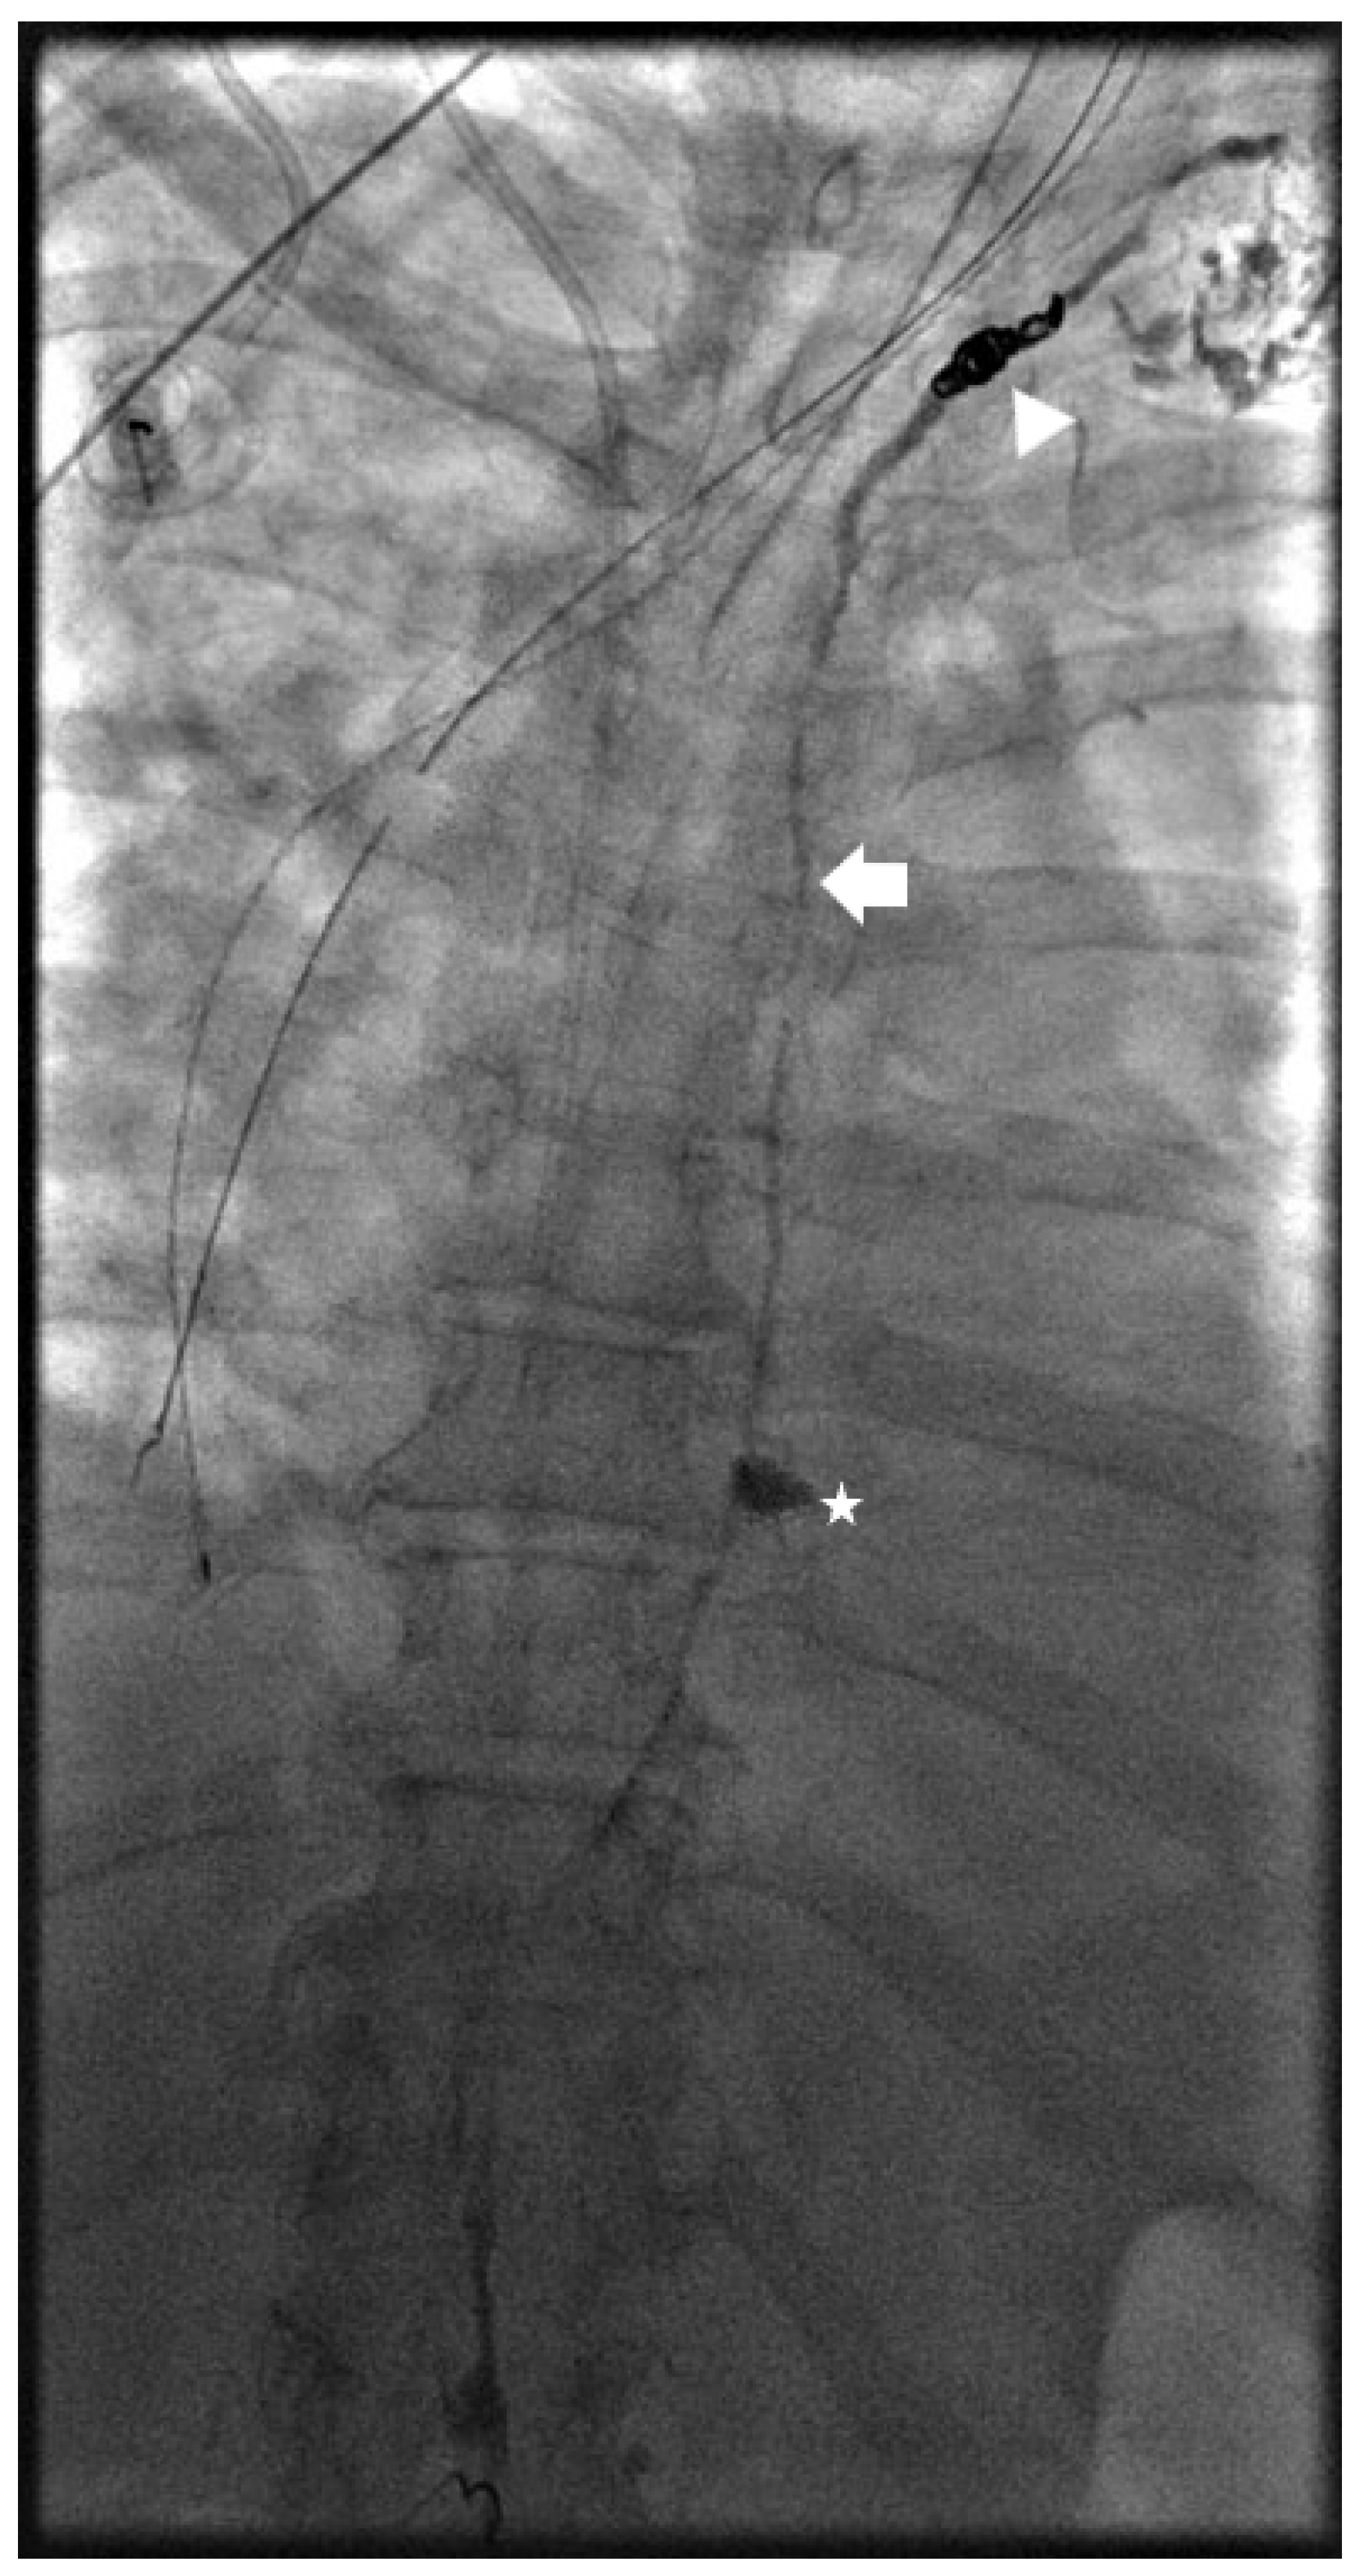

Kaminski et al. compared lymphangiography only versus lymphangiography and embolization. The median amount of iodized oil (lipidol) used was 12 mL (range 8–20 mL) with 20 mL used in all cases of lymphangiography only. Embolization of the target lymph vessel was performed with coils and/or liquid embolics (Histoacryl) diluted with ratio 1:1–1:5. Coils were used in the embolization of large lymph vessels to prevent distal migration of glue to the venous system (Figure 3 and Figure 4). Glue-only embolization was performed in peripheral lymphatics with no risk of glue migration or lymph node embolization. When embolization was not feasible, interstitial lymph node embolization was performed. Dietary restriction with Medium Chain Triglyceride supplement was prescribed for 2–3 days post-procedure. Embolization achieved 26/28 (92.9%) and 11/12 (91.7%) clinical success in traumatic and non-traumatic thoracic chylous effusion, respectively; lymphangiography only achieved 1/2 (50.0%) and 1/6 (16.7%) in traumatic and non-traumatic thoracic chylous effusion, respectively. Clinical success in combined abdominothoracic chylous effusion was achieved in 2/3 (66.7%) and 0/5 (0.0%) of embolization and lymphangiography only patients, respectively. Overall success of thoracic intervention was 39/48 (81.3%) with a significant difference between traumatic and non-traumatic groups. Complications were seen after lymphatic embolization in 5 patients with one grade 1, two grade 2, one grade 3, and one grade 4 as follows: pulmonary glue migration, upper extremity vein thrombosis, edematous pancreatitis, bleeding from branch of left hepatic artery, biliary peritonitis [22].

Figure 4.

Spot image from the same patient in Figure 3 showing lipiodol within the thoracic duct (arrow) and coils at the distal thoracic duct (arrowhead) to address a leak in the mediastinum (star).